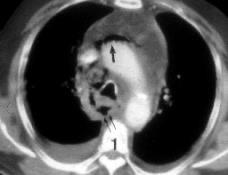

1/300 autopsias. Broncoscopia ..0,7%.

5ª-6ª décadas. + Varones.

2/3 inferiores de tráquea y bronquios principales. Sólo pared anterior y laterales. + Asintomáticos

Prince JS et-al. Nonneoplastic lesions of the tracheobronchial wall: radiologic findings with bronchoscopic correlation. Radiographics. 2002/ Shrof GS et al. Pathology of the Trachea and Central Bronchi. Semin Ultrasound CT MRI 2016